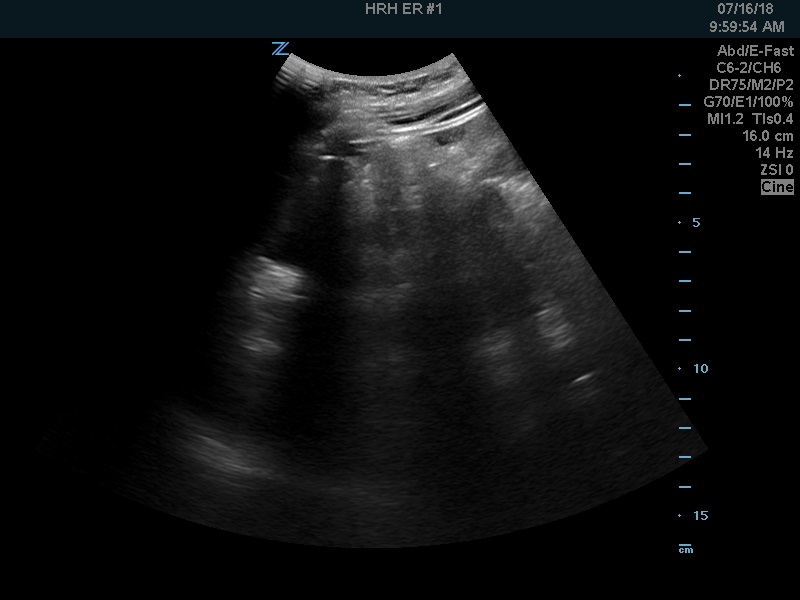

After examining her I started by scanning for free fluid. Here is the RUQ:

And the LUQ:

Not that much, but positive. Onto the pelvis…